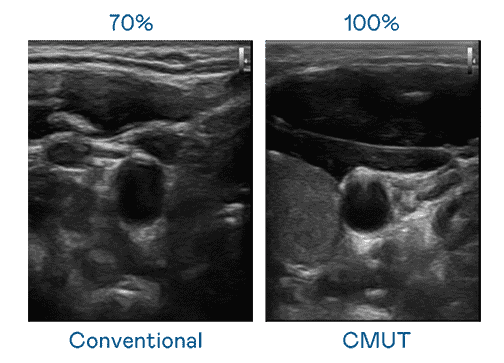

CMUT 技术是一种用电容式微机电元件来产生超音波讯号的技术。。。与传统 PZT 压电式技术相比,,,CMUT 频宽增加 30%,,,,更宽频的超音波讯号让影像解析度大幅提升,,,,是实现高影像品质医疗超音波扫描、、促进精准医疗发展的关键技术。。

大频宽带来超清晰影像

超音波影像的解析度高低,,,首先取决于探头能发出的讯号频宽。。。彩神vll CMUT 可提供高清晰的超音波讯号,,,提供高频宽、、高灵敏度、、、影像纹理细节更高的超音波影像,,,,协助医护人员缩短影像判读时间及利用精准的医疗影像进行诊断。。